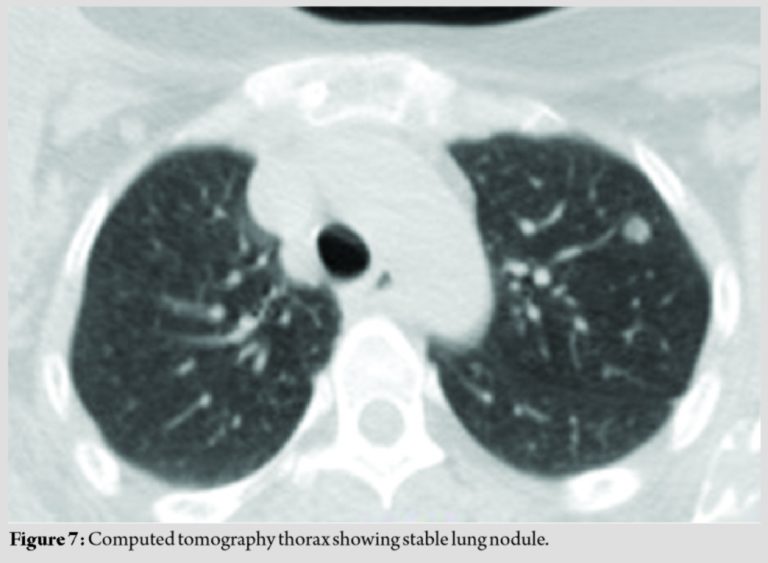

Radiological studies showed extensive lucent, ill-identified, “ground-glass” appearing lesions involving the entire right humerus (Fig. 2 and 3). There were incidental findings of similar lesions in both scapulae, right ulna, and left second metacarpal. Positron emission tomography scan showed avid lytic, expansile lesions involving the entire length of the right humerus, bilateral scapula, right ulna, and left second metacarpal. There were also lung nodules in the left upper lobe (≈8mm) and lower lobe (≈5mm) as well as in the right middle lobe (≈7mm).

CT-guided biopsy of the lung lesions showed features compatible with atypical adenomatous hyperplasia of the lungs with no evidence of malignancy.

The patient, after a follow-up of 2 years, is asymptomatic for her other lesions (Fig. 7).